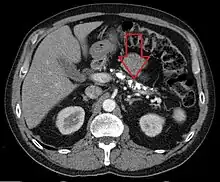

| Axial CT showing multiple calcifications in the pancreas in a patient with chronic pancreatitis | |

Computed tomography, magnetic resonance cholangiopancreatography (MRCP), and endoscopic ultrasound (EUS) all have similar sensitivity and specificity for diagnosing chronic pancreatitis.[4] MRCP is particularly utilized for its sensitivity in imaging the pancreatic ducts and bile ducts for associated changes such as stones or strictures.[4][12] A biopsy of the pancreas is not required for the diagnosis.[4] On imaging, pancreatic and bile duct dilatation, atrophy of the pancreas, multiple calcifications of the pancreas, and enlargement of pancreatic glands can be found.[12]